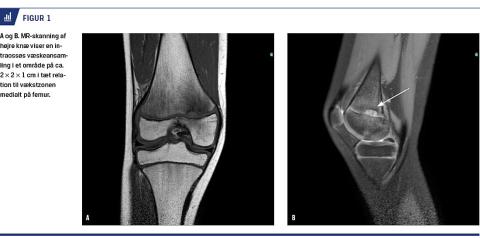

En ellers rask og aktiv tiårig pige fik under et fodboldskoleophold, hvor den daglige aktivitet blev væsentligt øget, ondt i højre knæ. Ved den første henvendelse hos egen læge havde smerterne varet i lidt over en måned. Hun havde svært ved at bøje knæet mere end 90 grader og havde smerter ved løb og gang. Smerterne blev beskrevet som værende »inde i knæet«. Hun havde ikke været alment påvirket, haft infektionstegn, feber eller natlige smerter på noget tidspunkt. Der var også symptomfri dage. Objektivt var det eneste positive fund smerter i det mediale kollateralligament. Vurderingen var en grad I-distorsion samt overbelastning og blev behandlet efter principperne om rest, ice, compression and elevation. Ved opfølgning tre uger senere var smerterne forværret ved enhver form for aktivitet, og hun blev henvist til en idrætsmedicinsk klinik til nærmere udredning. Her var den kliniske mistanke, at der var tale om pes anserinus-syndrom og meniskskade. En MR-skanning af højre knæ gav mistanke om OM pga. en intraossøs væskeansamling i tæt relation til vækstzonen medialt på femur (Figur 1).